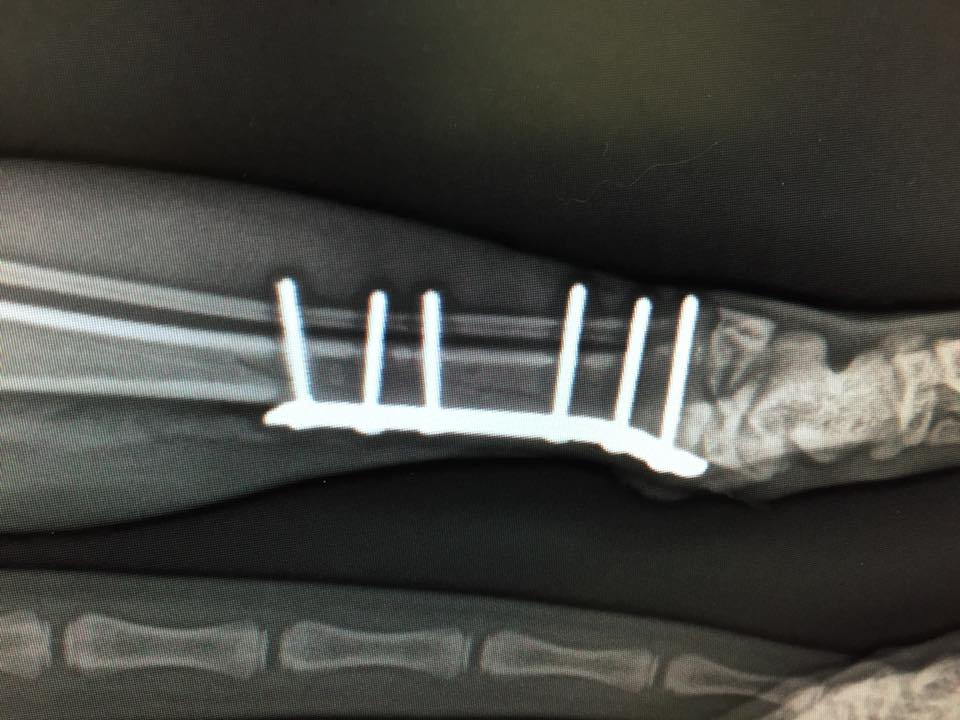

Der Umstand, warum dieser kleine Kerl zu uns kam, ist weniger erfreulich. Er brach sich das Bein so unglücklich, dass keine andere Option blieb als es operativ zu stabilisieren. Die Fraktur wurde mit einer Plattenosteosynthese mit sechs Schrauben versorgt und die Operation verlief komplikationslos und sehr zufriedenstellend. Der kleine Mann hat beste Chancen ein beschwerdefreies Leben zu führen.

In drei Monaten werden wir die Implantate wieder entfernen.